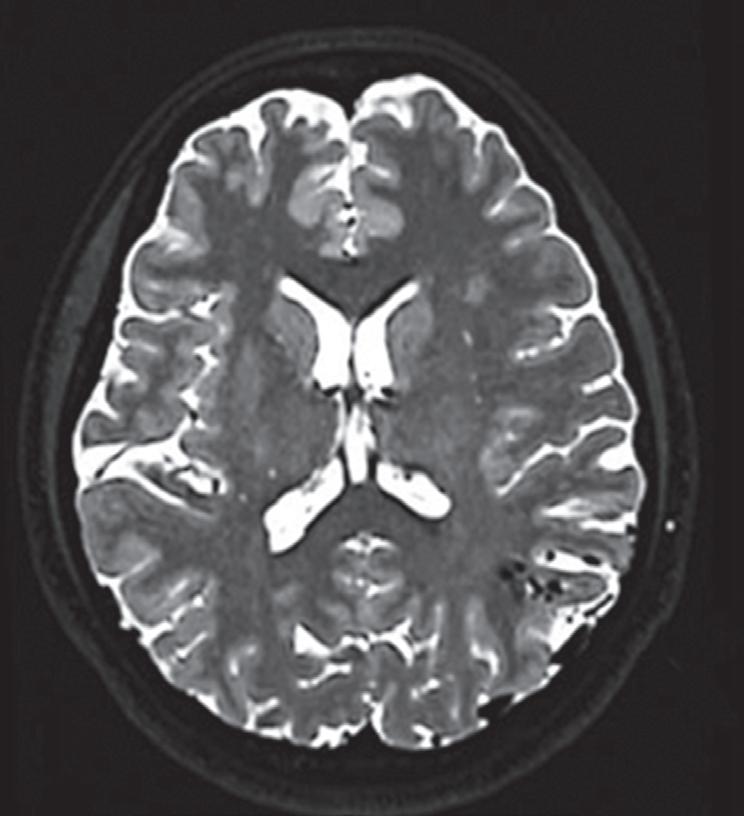

Fig. 1-8. (a-c) RNM T1 com contraste, cortes sagital (a), coronal (b) e axial (c) demonstrando MAV não rota com nidus localizado no lobo occipital à esquerda (setas longas). (d) Arteriografia digital cerebral com injeção de contraste via carótida direita (AP) mostrando a contribuição da carótida direita na irrigação da MAV contralateral. (e,f) Com injeção de contraste via carótida esquerda, em Perfil e AP respectivamente, observa-se nidus compacto nutrido por ramos da artéria cerebral média à esquerda e a veia de drenagem precoce se dirigindo para o seio sagital superior. Projeções em AP (g) e em perfil (h) demonstrando a contribuição do sistema vertebrobasilar por meio de ramos distais da artéria cerebral posterior à esquerda e drenagem para os seios sagital superior e sigmoide à esquerda (setas curtas).

Fig. 1-9. RNM T2 em cortes (a) axial e (b) sagital. (c,d) Tractografia axial – sagital, demonstrando a posição de uma MAV não rota localizada na superfície basal do lobo frontal, nos giros orbitários e reto à direita (setas longas). Arteriografia digital cerebral com injeção de contraste via carótida direita, (e) AP e (f) em perfil demonstrando MAV nutrida por ramos da artéria cerebral média e cerebral anterior direita e drenagem para o seio sagital superior (seta curta).